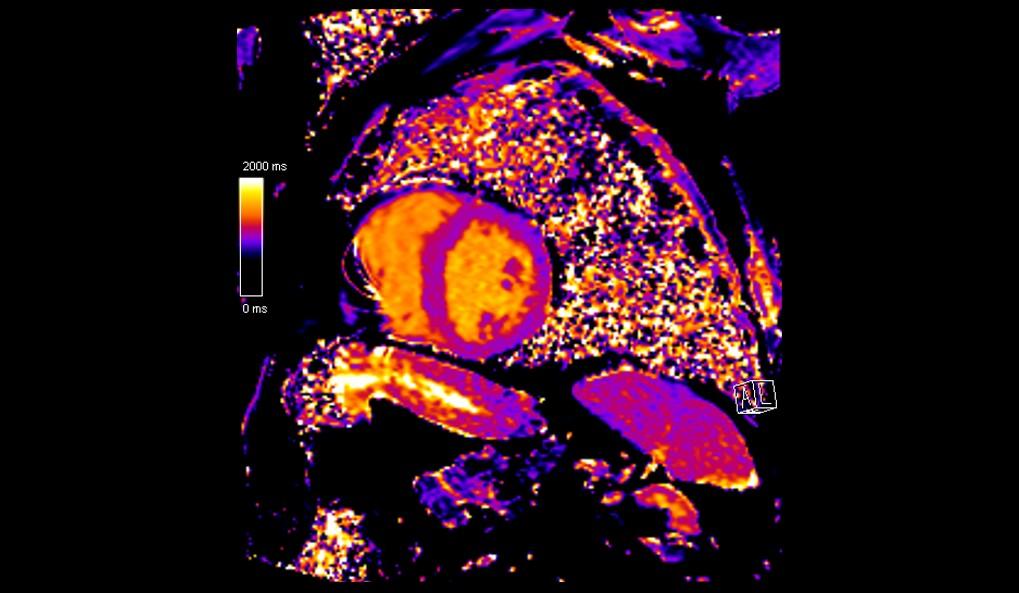

El examen de RMC se realizó en el equipo MAGNETOM Altea 1.5T. Se realizaron secuencias de CINE PSIF, FSE black-blood T1 y T2, phase-contrast, mapeo miocárdico (MyoMaps) T1/T2/T2* y LGE TRUFI high-resolution después de la inyección de contraste (DOTA-Gd 0,5M 0,2mmol/kg).

La RMC evidenció dilatación biatrial importante (AD=170ml/m2 y AE=120ml/m2), dilatación biventricular discreta (VDFVD=115ml/m2 y VDFVE=103ml/m2), FEVD 49%, FEVI 45%, rectificación del septo interventricular, insuficiencia tricúspide moderada, derrame pericárdico discreto, realce tardío heterogéneo en VI de patrones mesocárdico y subendocárdico en segmentos anteriores, anteroseptales, inferoseptales, inferiores y anterolaterales con distribución predominante medio-basal y realce tardío biatrial estadio UTAH IV. El MyoMaps en septo interventricular reveló elevaciones de tiempos T1 nativo (1070ms), T2 (58ms) y del volumen extracelular (33%) con T2* normal (28ms).

Los hallazgos de la RMC son compatibles con el diagnóstico de amiloidosis cardíaca. El patrón de cardiomiopatía dilatada con realce tardío (fibrosis) multisegmentar en VI, evitando segmentos apicales, elevaciones de T1 y VEC y fibrosis biatrial son hallazgos típicos de amiloidosis, especialmente en el subtipo ATTR. La Resonancia Magnética del Corazón, a través de su evaluación multiparamétrica, permite una diferenciación etiológica precisa de las cardiomiopatías, siendo indicada por las mejores guías como examen diagnóstico de primera línea en la investigación de insuficiencia cardíaca.